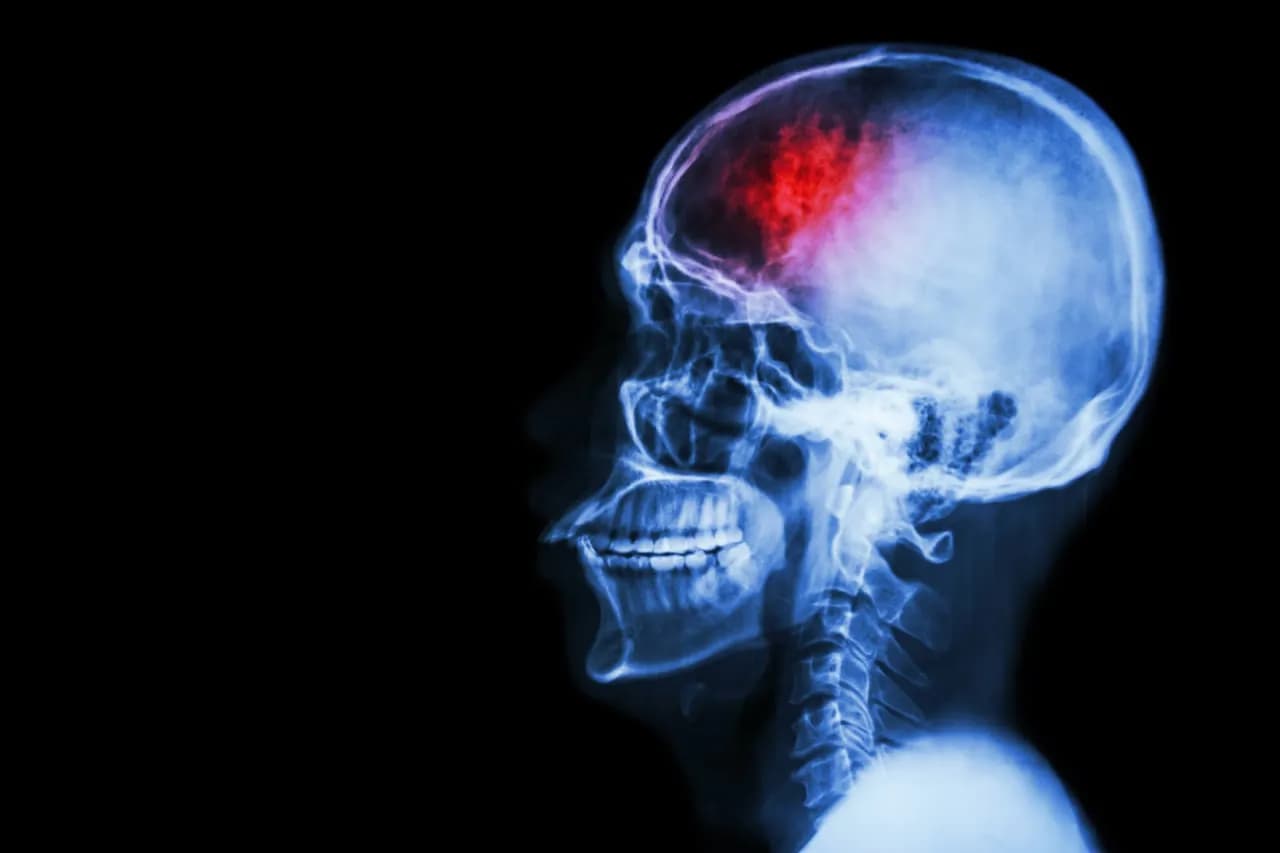

Udar mózgu można podzielić na dwa główne typy: udar niedokrwienny oraz udar krwotoczny. Udar niedokrwienny, który występuje w około 85% przypadków, jest wynikiem zablokowania tętnic mózgowych. W przeciwieństwie do tego, udar krwotoczny występuje, gdy dochodzi do pęknięcia naczynia krwionośnego, co prowadzi do krwawienia wewnątrz mózgu. Różnice te mają duże znaczenie dla sposobu leczenia pacjentów. W przypadku udaru niedokrwiennego kluczowe jest szybkie podanie trombolityków, które pomagają rozpuścić skrzep. Natomiast udar krwotoczny często wymaga zabiegów chirurgicznych, aby zatrzymać krwawienie i usunąć gromadzącą się krew.Czytaj więcej: Jak skutecznie chronić się przed udarem mózgu dzięki zmianom w diecie i stylu życia